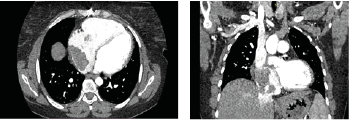

Thoracic Aorta CT Angiography

Cardiac enlargement was observed. The right atrium was dilated, and a lobulated mass measuring 62 × 40 × 46 mm was detected within the right atrium. Vascular structures were noted at the superior aspect of the mass. The lesion extended slightly through the tricuspid valve into the right ventricle and minimally toward the inferior vena cava.

Figure 2 A and 2B: The right atrium was dilated, and a lobulated mass measuring 62 × 40 × 46 mm was detected within the right atrium.